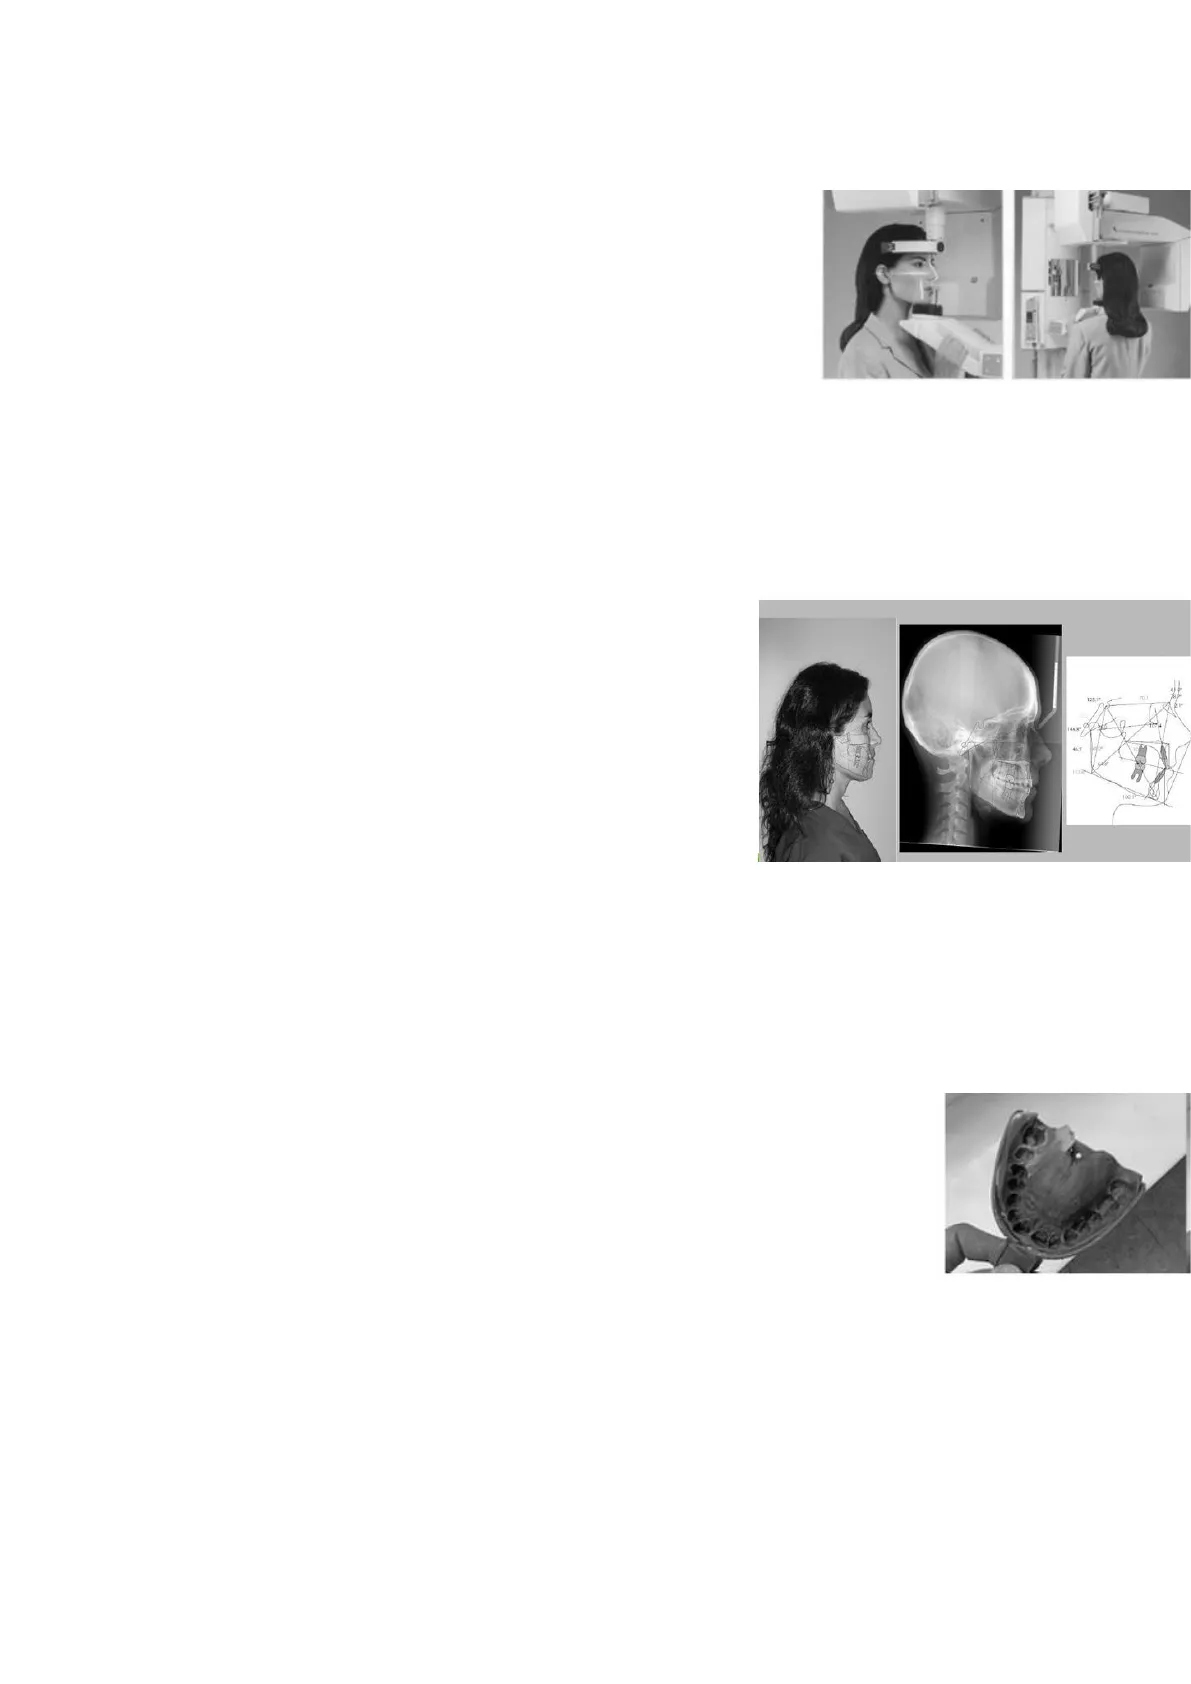

Cefalometría: fotografías y radiografías del paciente que se introducen en el ordenador y este las computeriza para uso informático.

El ordenador tiene incorporados datos obtenidos, previamente seleccionados, de una variedad de caras armónicas. Se comparan datos de la cefalometría con los almacenados en el ordenador. Se mide con exactitud la variación en milímetros que se debe realizar en las distintas partes de la cara para lograr el resultado deseado por el especialista y el paciente.

Aplicaciones: Estudio del crecimiento facial: repetición y reproducción de las estructuras del paciente. Superposición de trazados para estudiar su crecimiento. · Diagnóstico de posibles patologías especiales (traumatismos, hipertrofia adenoidea ... ). - Evaluación del espacio nasofaríngeo. - Diagnóstico de anomalías craneofaciales (clase II, clase III ... ). - Seguimiento y evaluación de los resultados obtenidos en el tratamiento.